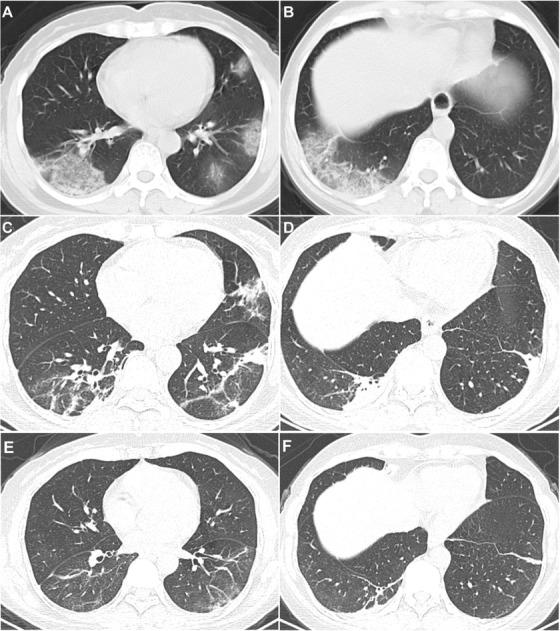

Thalidomide combined with low-dose short-term glucocorticoid in the treatment of critical Coronavirus Disease 2019.

Clin Transl Med. 2020 Jun;10(2):e35. doi: 10.1002/ctm2.35. Epub 2020 Jun 4.